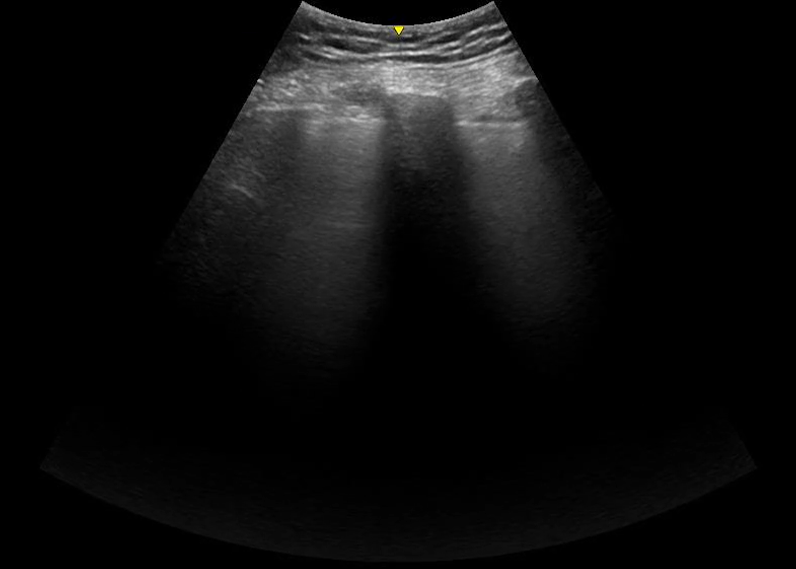

Below are examples of images obtained with the probe in the conventional orientation – perpendicular to the ribs with the probe maker up. Notice how much clearer the lung sliding is in shallow image taken with the linear probe.

Specifically, if you are looking for lung sliding, you need to use a setting with very little depth so that the pleura is prominent on the screen. A linear probe is ideal, but a curvilinear probe with the depth dialed way down is fine as well.

If you are looking for B lines (which is what differentiates wet lungs from dry lungs), you need more depth to the image. B lines – by definition – do not fade. They reach the far edge of the image no matter how deep the image settings are. That is opposed to comet tail artifact, which is a normal finding. A comet tail artifact, like a B line, is a vertical white line that originates at the pleura and moves with the sliding lung. However, unlike a B line, they are short and fade away without reaching the deepest edge of the image. Depth neatly separates the two. A curvilinear probe is nice for achieving that depth and has the added benefit of letting you see several rib space at once. (Multiple rib spaces are handy because the differential for diffuse B lines is very different from that for focal B lines.)